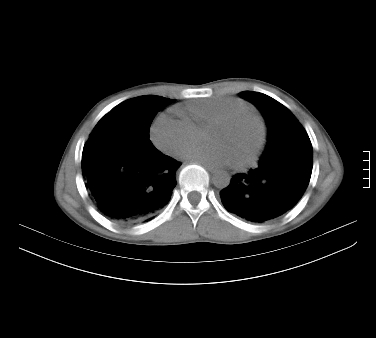

患者,男,17岁,系我院急诊科收治的一例百草枯中毒患者,做ct检查时,距离服药的时间为3天。上传与大家分享

补充:百草枯进入人体内主要分部于肺和骨骼,肺部损伤24小时内出现水肿,2-3天内出现急性呼吸窘迫综合征,1-2周内出现肺纤维化。(引自陈灏珠,实用内科学12版)